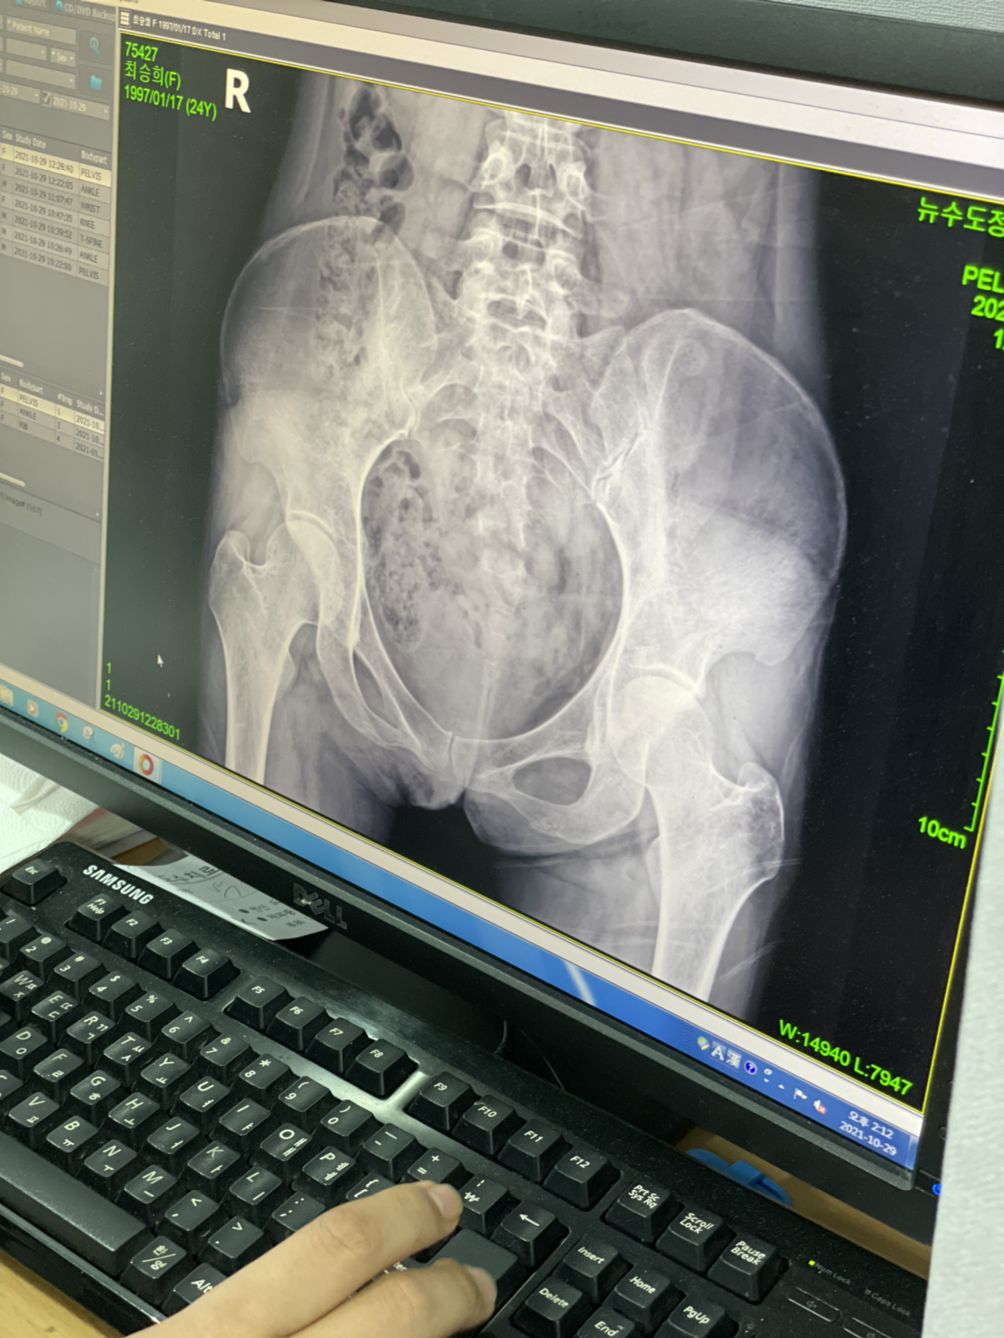

골반이 삐뚤어졌대

종형외과...

넘비싸...8ㅅ8 근데 너무아프고...ㅋㅋㅋ 많이 삐둘어지긴한듯